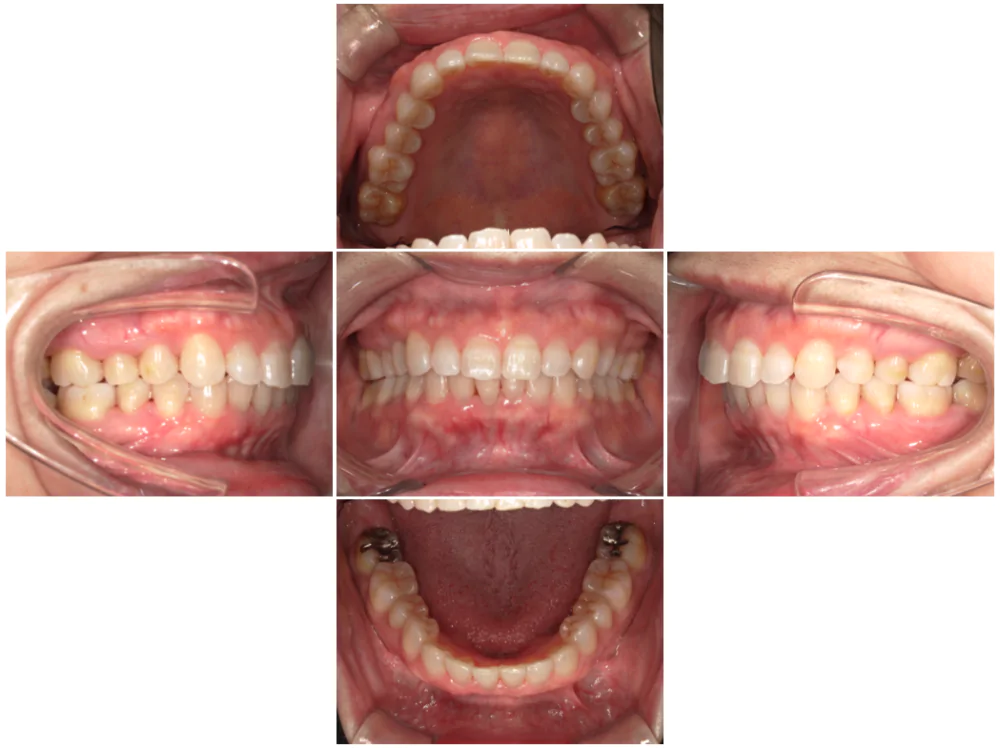

症例3

| 来院時の主訴 | 歯の間の隙間を閉じたい |

| 医院での対応や適用装置 | マウスピース矯正装置を使用して主訴である歯の間の隙間を閉じて改善を行いました。 歯の隙間の原因は飲み込み時に舌を前に出してしまう癖だと考えられましたので、 トレーニングを行い癖も無くなりました。 |

| 通院期間 | 6ヶ月 |

| 通院回数 | 5回 |

| 治療費用総額 | 577,500円(税込) |

| リスクと副作用 | 矯正治療による歯の移動に伴う痛み、歯根吸収、虫歯 |